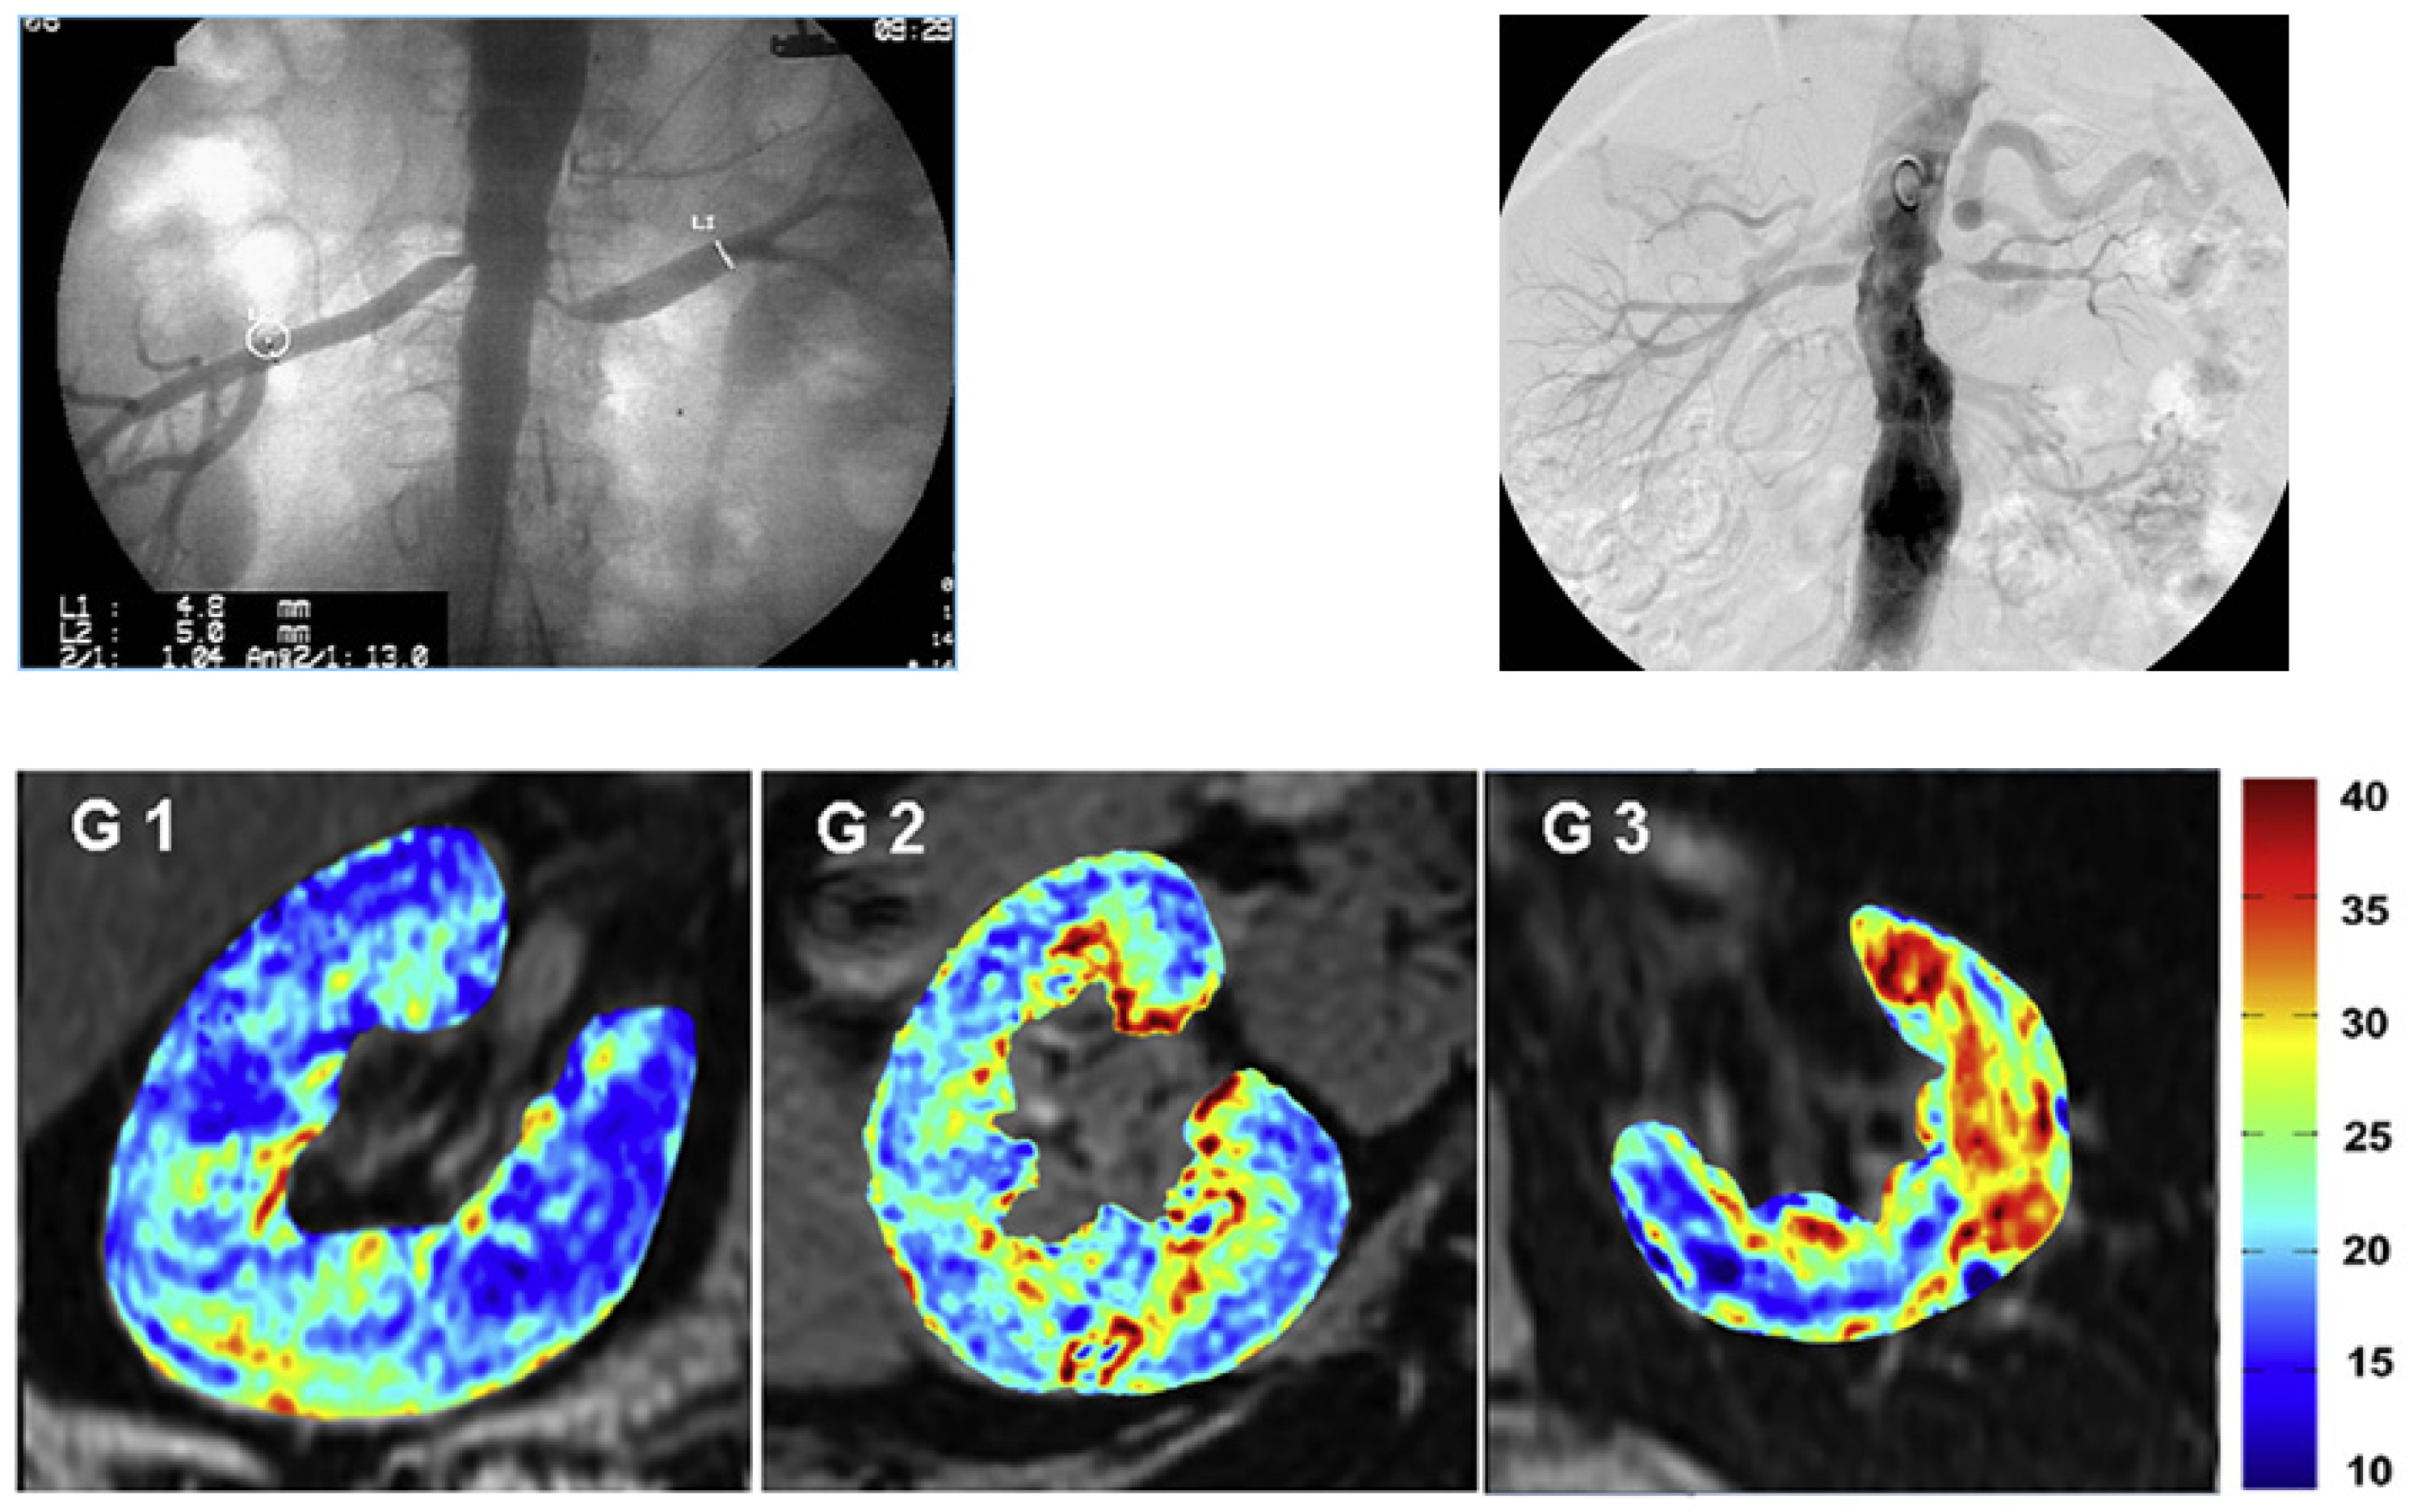

- Saad, A.; Crane, J.; Glockner, J.F.; Herrmann, S.M.S.; Friedman, H.; Ebrahimi, B.; Lerman, L.O.; Textor, S.C. Human renovascular disease: Estimating fractional tissue hypoxia to analyze blood oxygen level-dependent MR. Radiology 2013, 268, 770–778. [Google Scholar] [CrossRef]

- Textor, S.C.; Glockner, J.F.; Lerman, L.O.; Misra, S.; McKusick, M.A.; Riederer, S.J.; Grande, J.P.; Gomez, S.I.; Romero, J.C. The use of magnetic resonance to evaluate tissue oxygenation in renal artery stenosis. J. Am. Soc. Nephrol. 2008, 19, 780–788. [Google Scholar] [CrossRef]

- Gloviczki, M.L.; Glockner, J.F.; Lerman, L.O.; McKusick, M.A.; Misra, S.; Grande, J.P.; Textor, S.C. Preserved oxygenation despite reduced blood flow in poststenotic kidneys in human atherosclerotic renal artery stenosis. Hypertension 2010, 55, 961–966. [Google Scholar] [CrossRef]

- Gloviczki, M.L.; Glockner, J.F.; Crane, J.A.; McKusick, M.A.; Misra, S.; Grande, J.P.; Lerman, L.O.; Textor, S.C. Blood oxygen level-dependent magnetic resonance imaging identifies cortical hypoxia in severe renovascular disease. Hypertension 2011, 58, 1066–1072. [Google Scholar] [CrossRef] [PubMed]

- Abumoawad, A.; Saad, A.; Ferguson, C.M.; Eirin, A.; Herrmann, S.M.; Hickson, L.J.; Goksu, B.B.; Bendel, E.; Misra, S.; Glockner, J.; et al. In a Phase 1a escalating clinical trial, autologous mesenchymal stem cell infusion for renovascular disease increases blood flow and the glomerular filtration rate while reducing inflammatory biomarkers and blood pressure. Kidney Int. 2020, 97, 793–804. [Google Scholar] [CrossRef]

- Herrmann, S.M.; Saad, A.; Eirin, A.; Woollard, J.; Tang, H.; McKusick, M.A.; Misra, S.; Glockner, J.F.; Lerman, L.O.; Textor, S.C. Differences in GFR and Tissue Oxygenation, and Interactions between Stenotic and Contralateral Kidneys in Unilateral Atherosclerotic Renovascular Disease. Clin. J. Am. Soc. Nephrol. 2016, 11, 458–469. [Google Scholar] [CrossRef]